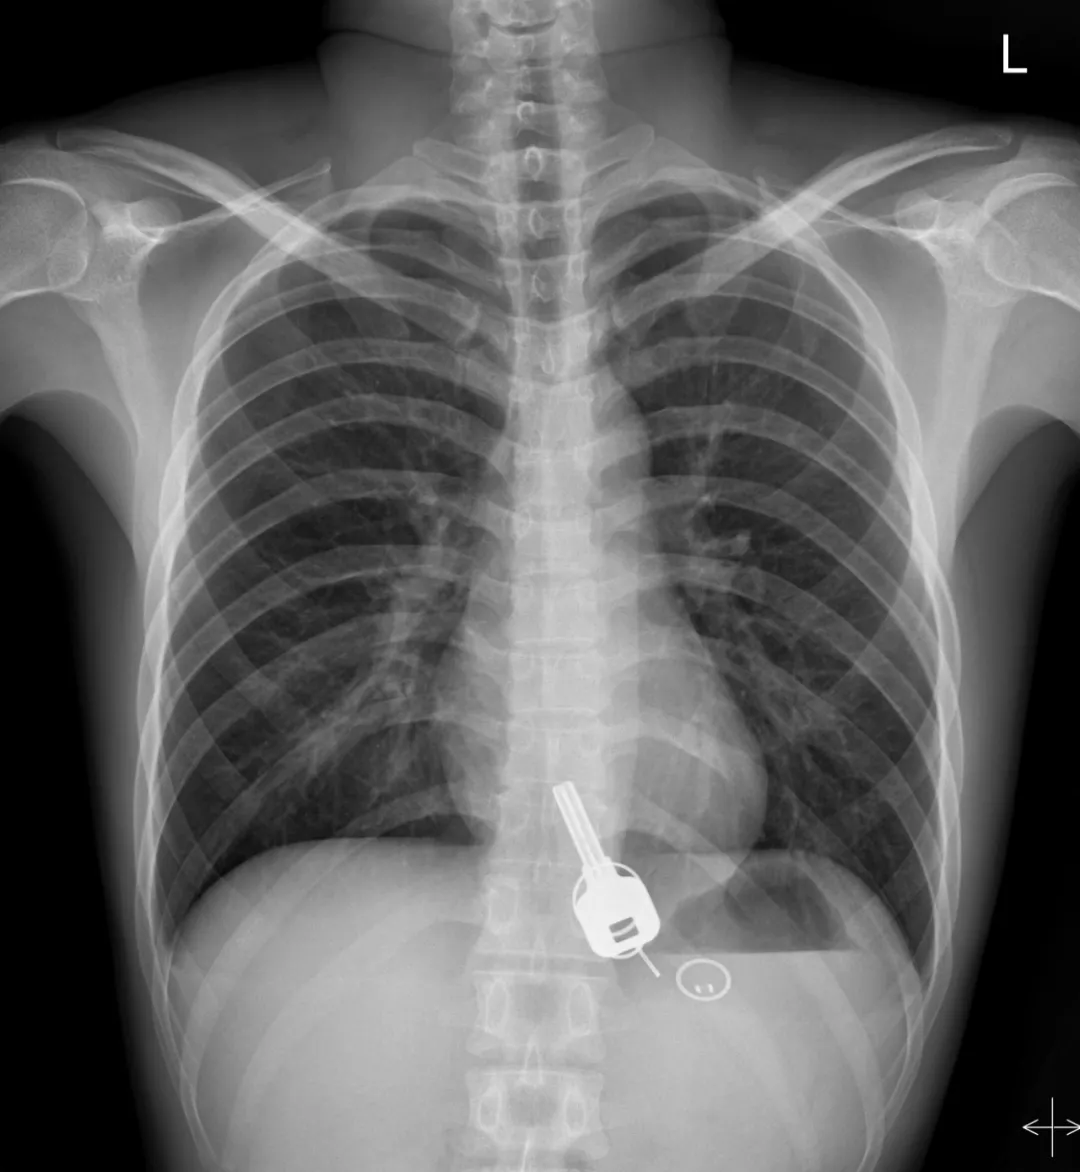

廣東東莞的常先生酒后回家找不到鑰匙,酒醒后他感到胸口疼痛,去醫(yī)院一查,發(fā)現(xiàn)一把鐵鑰匙、2個鑰匙扣、1個門禁牌清楚顯示在肚子胃區(qū)的位置上。